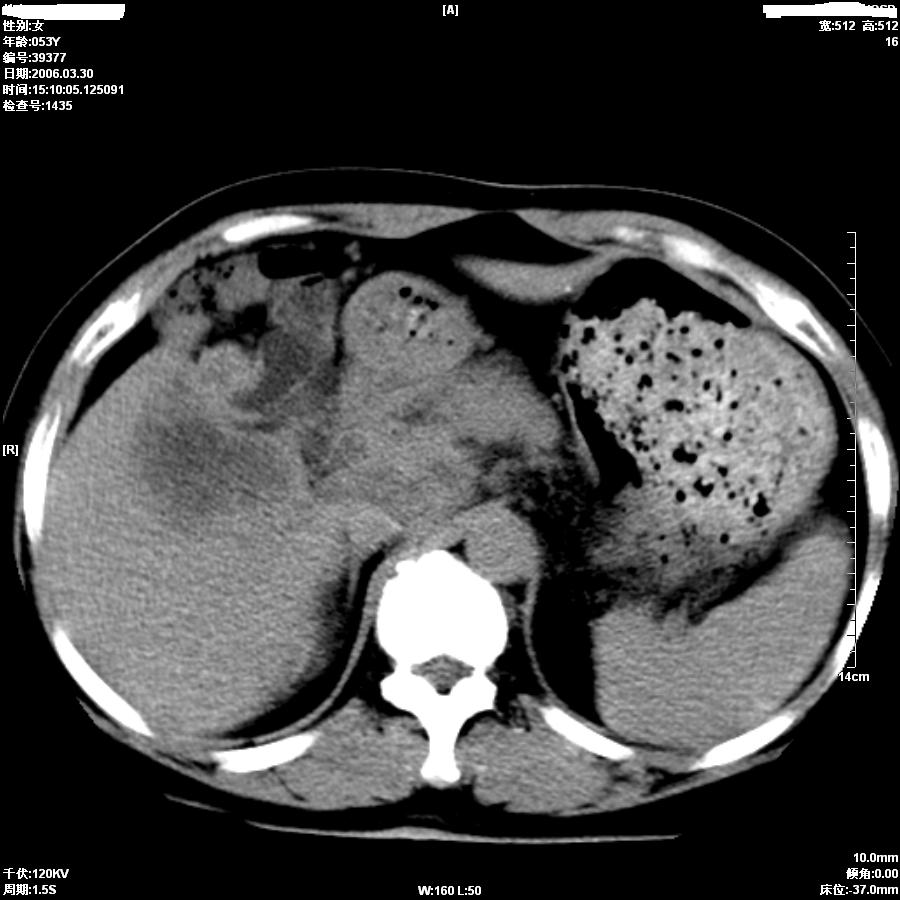

女,50岁,上腹部憋胀,疼痛月余。做增强刚打了50ml造影剂病人就出现了较重的过敏,所以强化不成功。

支持肝癌伴左叶外侧段肝内胆管轻度扩张。

平扫第8图胆总管内似见结石,上部胆道扩张,肝内片影无强化,胆囊不清,胃小弯壁略厚。

考虑1胆结石伴低微弹道梗阻及肝内感染2胆管癌。

因为没有完整的强化,该病例我首先考虑是肝内胆管细胞癌.患者因为有过敏我建议行mri.

从平扫:肝脏肿块,胰头周围结构不清似有结节。考虑恶性肿瘤(首先要排外肝胆感染病变)。胆管癌>肝癌。建议mri。

较典型胆管癌。

胆管细胞癌可能性大

胆总管扩张,未见明显结石征象。还是胆管细胞ca可能大

提示肝内胆管细胞癌。

肝内胆管癌 累及肝门

如果胆囊未切除,首先考虑胆囊癌肝侵犯。

中老年妇女,肝门、胆囊区病变,病变实体形态欠清楚,胆囊癌可能性极大。

鉴别诊断:肝癌;胆管癌;

理由:1、低密度病灶,动脉期末有一点强化。

2、左肝内胆管扩张。

3、肝门区胆管壁静脉期有强化。